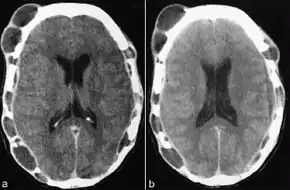

Tests usually include imaging using MRI.[5] Findings include breakdown of bone and thickening of the pituitary stalk. The perivascular space may appear prominent, the pituitary gland cystic and there may be signs in the white matter, a mass in the hypothalamus and enhancement of the meninges.[5]